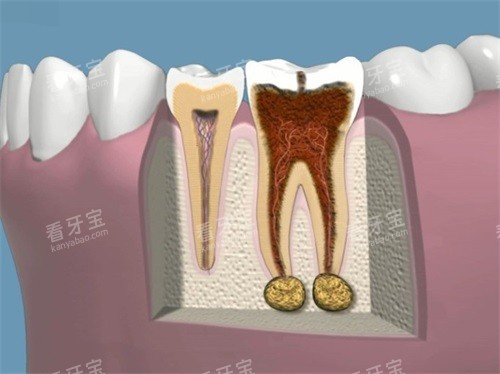

正定芽贝口腔引进了一系列可靠的口腔诊疗设备,如智能化口腔全景机、口腔CT、种植机、根管治疗仪等。

智能化口腔全景机能够快速、较准地拍摄口腔全景图像,为医生提供齐全的口腔信息,有助于更更准一些地诊断口腔疾病;口腔CT则能够提供更详细的口腔三维影像,对于复杂的口腔疾病诊断和治疗方案的制定具有重要意义;种植机和根管治疗仪等设备则为种植牙、根管治疗等口腔手术的顺利开展提供了有力维持。